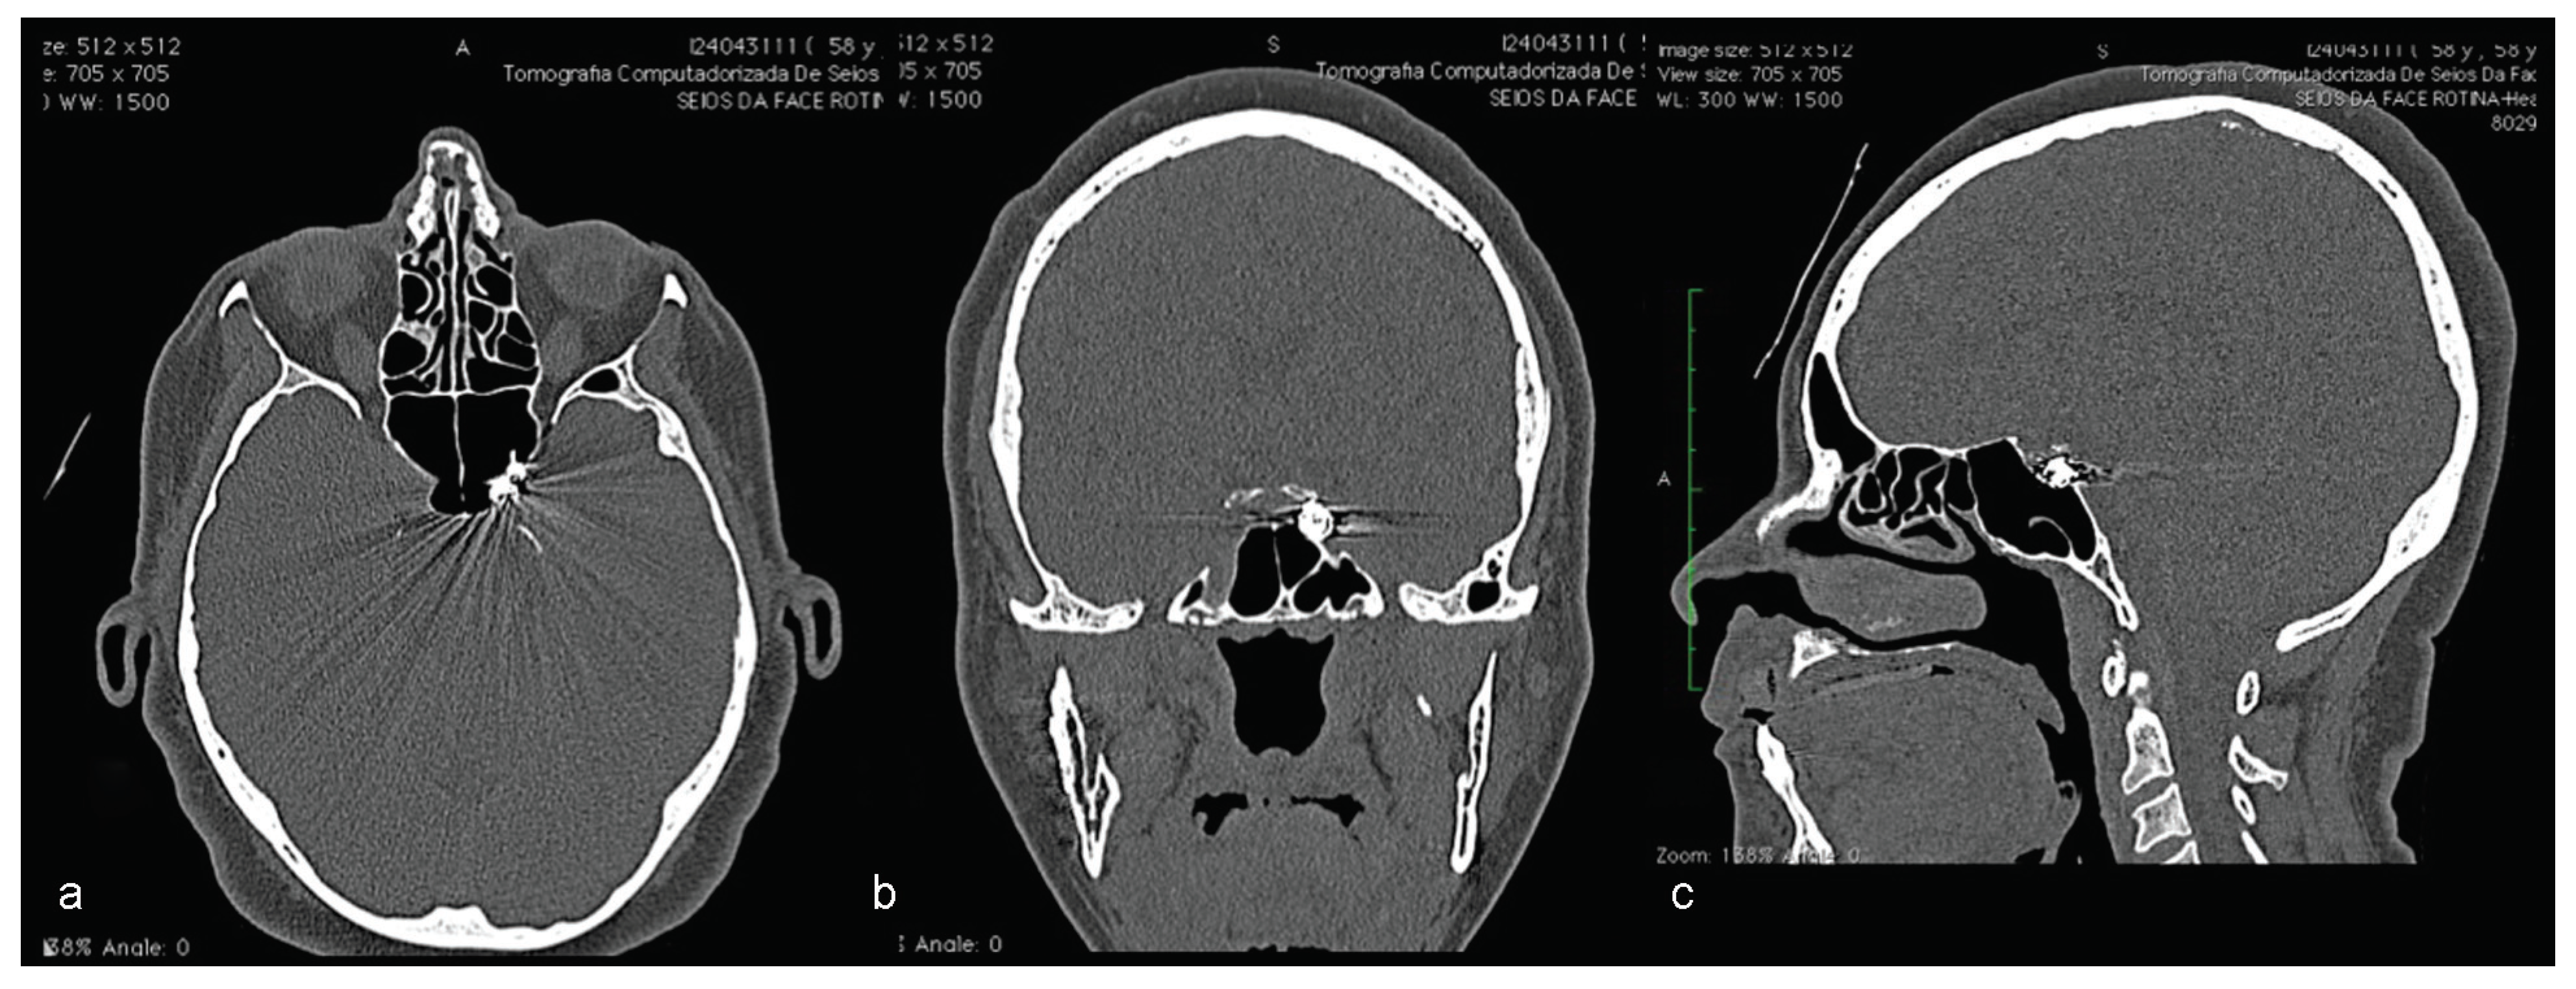

A computed tomography (CT) was performed in a fourchannel spiral CT scanner (Toshiba Asteion 4; Toshiba, Tokyo, Japan) with axial, coronal, and sagittal views. Multiple frac-tures were identified on the face (Figure 2 and Figure 3) and on the left side of the SS region (Figure 4).

Figure 2. (a–d) CT windows displaying multiple fractures in the middle third of the face or midface.